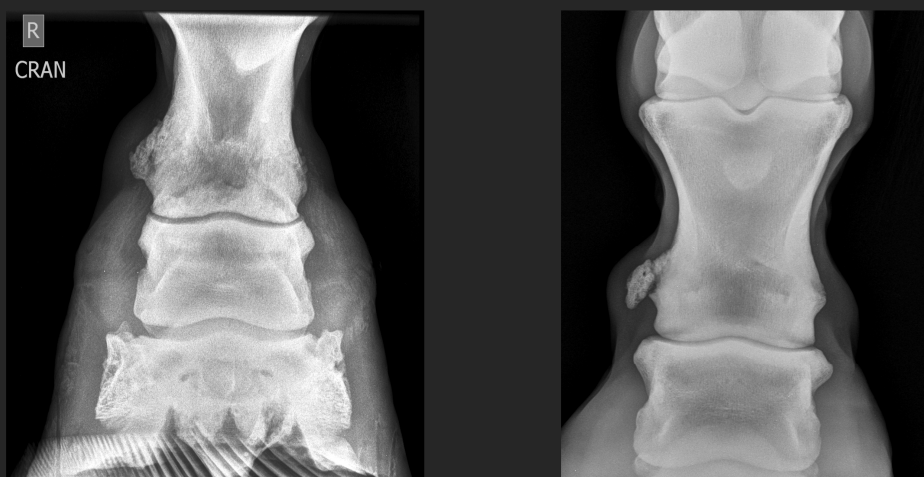

nodular lymph edema

pedal bone ventral rotation with sinking